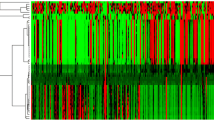

Univariate and multivariate analyses identified 40, 2003, and 45 quantitative features associated with distant metastasis, nodal metastasis, and histopathology (adenocarcinoma and squamous cell carcinoma), respectively. A machine learning model yielded the highest areas under the receiver operating characteristic curves of 0.92, 0.84, and 0.88 to predict the same previous patterns.

Several radiomic features (including wavelet energies, information measures of correlation and maximum probability from co-occurrence matrix, busyness from neighborhood intensity-difference matrix, directionalities from Tamura’s texture, and fractal dimension estimation) significantly associated with distant metastasis, nodal metastasis, and histology were discovered in this work, presenting great potential as imaging biomarkers for pathological diagnosis and target therapy decision.